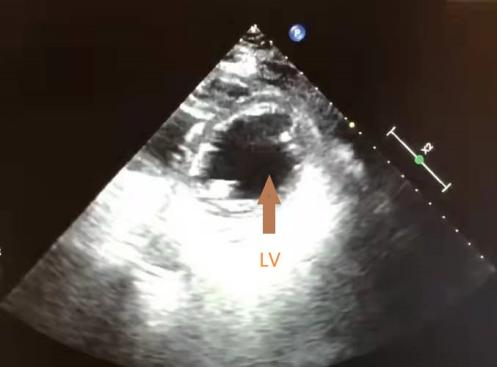

初步诊断患者为休克、心包积液、肺部感染、代谢性酸中毒。为解除心包压塞,于6月27日在血管造影下行心包穿刺引流术,引流量为220 mL,接引流袋(后持续引流出50 mL积血),术后超声心动图提示心功能正常。第2日患者胸闷症状好转,仍有心前区疼痛,给予地佐辛镇痛; 接下来的三日内患者心前区疼痛较前好转,超声心动图提示无明显心包积液,但出现持续性的发热,持续给予碳青霉烯类抗生素抗感染治疗。第6日复查超声心动图提示左室室间隔近心尖处有一液性暗区,并随心动周期晃动(图 1),大小约为1.5 cm×1.0 cm,左心室射血分数为70%,患者神志清楚,无胸闷呼吸困难,偶有心前区疼痛,无血流动力学异常,故未予以任何特殊治疗。第8日超声心动图示液性暗区仍然存在但范围缩小,大小约为1.1 cm×0.7 cm,患者胸痛症状较前缓解,血流动力学仍无异常,故仍未给予治疗,并转至急诊内科普通病房继续治疗。第11日超声心动图提示液性暗区消失(图 2)。第16日患者神志清楚,无胸闷胸痛,心肺听诊无明显异常,遂出院。至2021年12月,经过5个月的随访患者无心功能不全的表现,预后良好。

| LV为左心室 图 2 患者第11日超声心动图 |

经详细询问病史,结合超声心动图结果,本例患者“心包积液”诊断明确,给予心包穿刺引流解除心脏压塞等对症支持治疗,经积极治疗后患者病情好转,而后于复查的超声心动图中发现一处随心动周期晃动的液性暗区,且在未予以任何干预的情况下自行消失,笔者考虑可能是由于心脏因针刺外伤导致的心肌内解剖血肿(intramuscular anatomy of haematoma, IDH)。